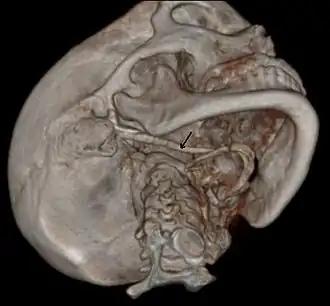

3D-reconstructed CT scan showing bilateral stylohyoid ligament ossification -